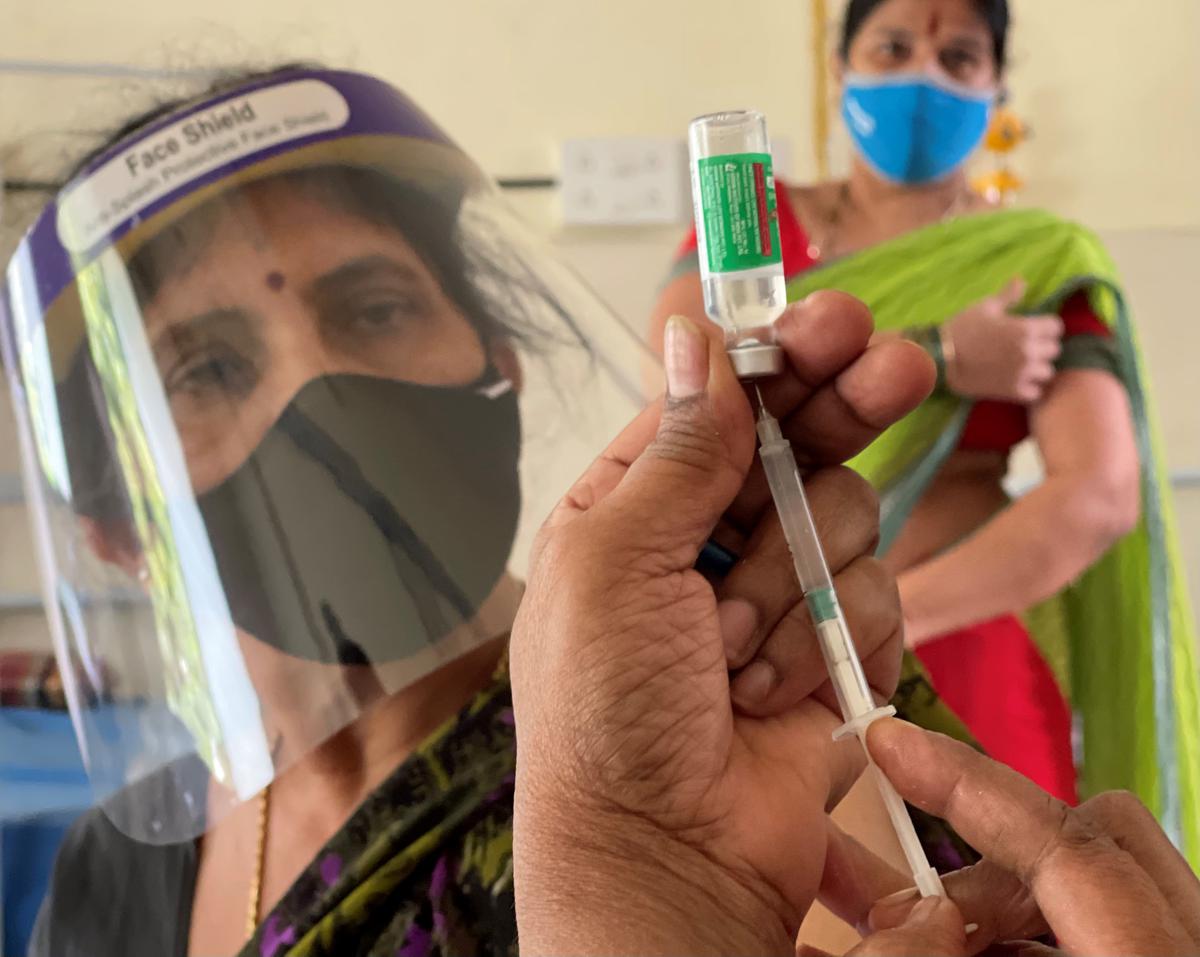

India faces a challenge with its mass vaccination efforts

India COVID-19 Vaccine Tracker

Author: Akhil Kumar, William Joe, Abhishek Kumar, Atif Amin, Weiyu Wang, Rockli Kim, Rakesh Sarwal, S V Subramanian. India COVID-19 Vaccine Tracker for Districts and Parliamentary Constituencies of India. Apr 2021. Geographic Insights Lab at the Harvard Center for Population and Development Studies; Center for Geographic Analysis at Harvard University, Cambridge, MA

India’s vaccination programmes: Are we ready to protect our populations from growing health risks?